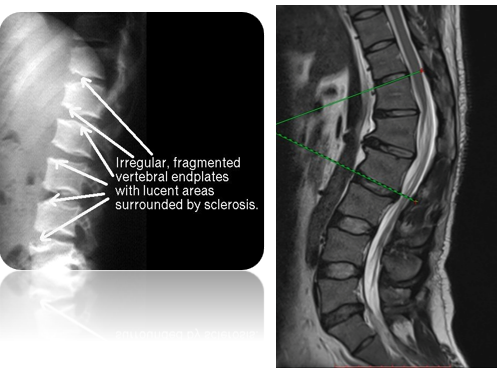

• xray - will see irregular fragmented vertebral endplates with translucent areas surrounded by sclerosis

• MRI - irregular narrowing as well as presence of scheuermanns nodes towards endplates